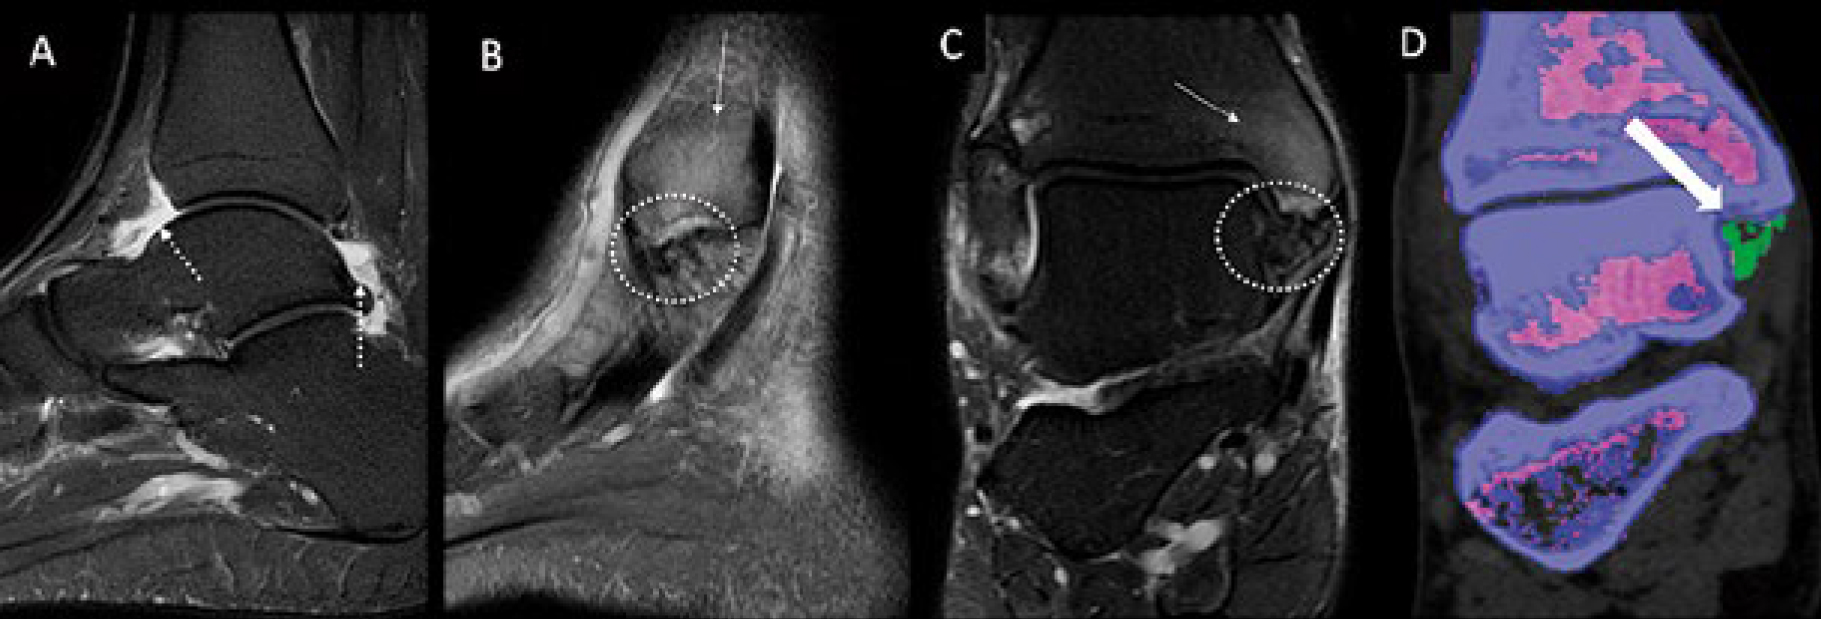

- Ortopedia: separação entre tecido ósseo e partes moles com alta precisão.

A Dual Energy CT oferece vantagens como menor necessidade de contraste iodado, imagens com melhor relação sinal/ruído e análise mais precisa de tecidos moles. Além disso, permite reconstruções com realce seletivo e geração de imagens virtuais sem osso ou sem contraste.